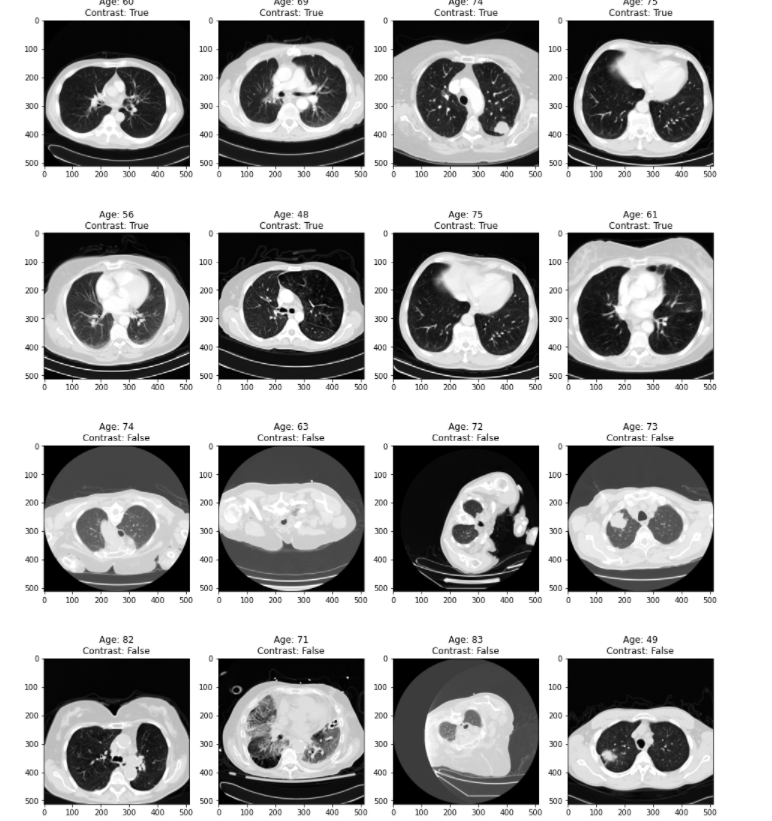

4. contrast 사용 여부가 다른 dicom 파일 시각화

## contrast 가 True인 이미지와 False인 이미지 섞어서 subset 생성

df = pd.read_csv('overview.csv')

df_contrast = df.loc[df.Contrast == True,:][:8]

df_none = df.loc[df.Contrast == False,:][:8]

df_subset =pd.concat([df_contrast, df_none]).reset_index(drop=True)

## subset의 시각화

f, ax = plt.subplots(4,4, figsize=(16,20))

for i, data in enumerate(df_subset.values):

path = 'dicom_dir/' + data[-1]

image = dicom_2_array(path)

ax[i//4, i%4].imshow(image, cmap='gray')

ax[i//4, i%4].set_title(f'Age: {data[1]}\nContrast: {data[2]}')

시각화를 했을 때 어떤 차이가 있는 것 같은가?

솔직히 말하면 나는 아직 잘 모르겠다.